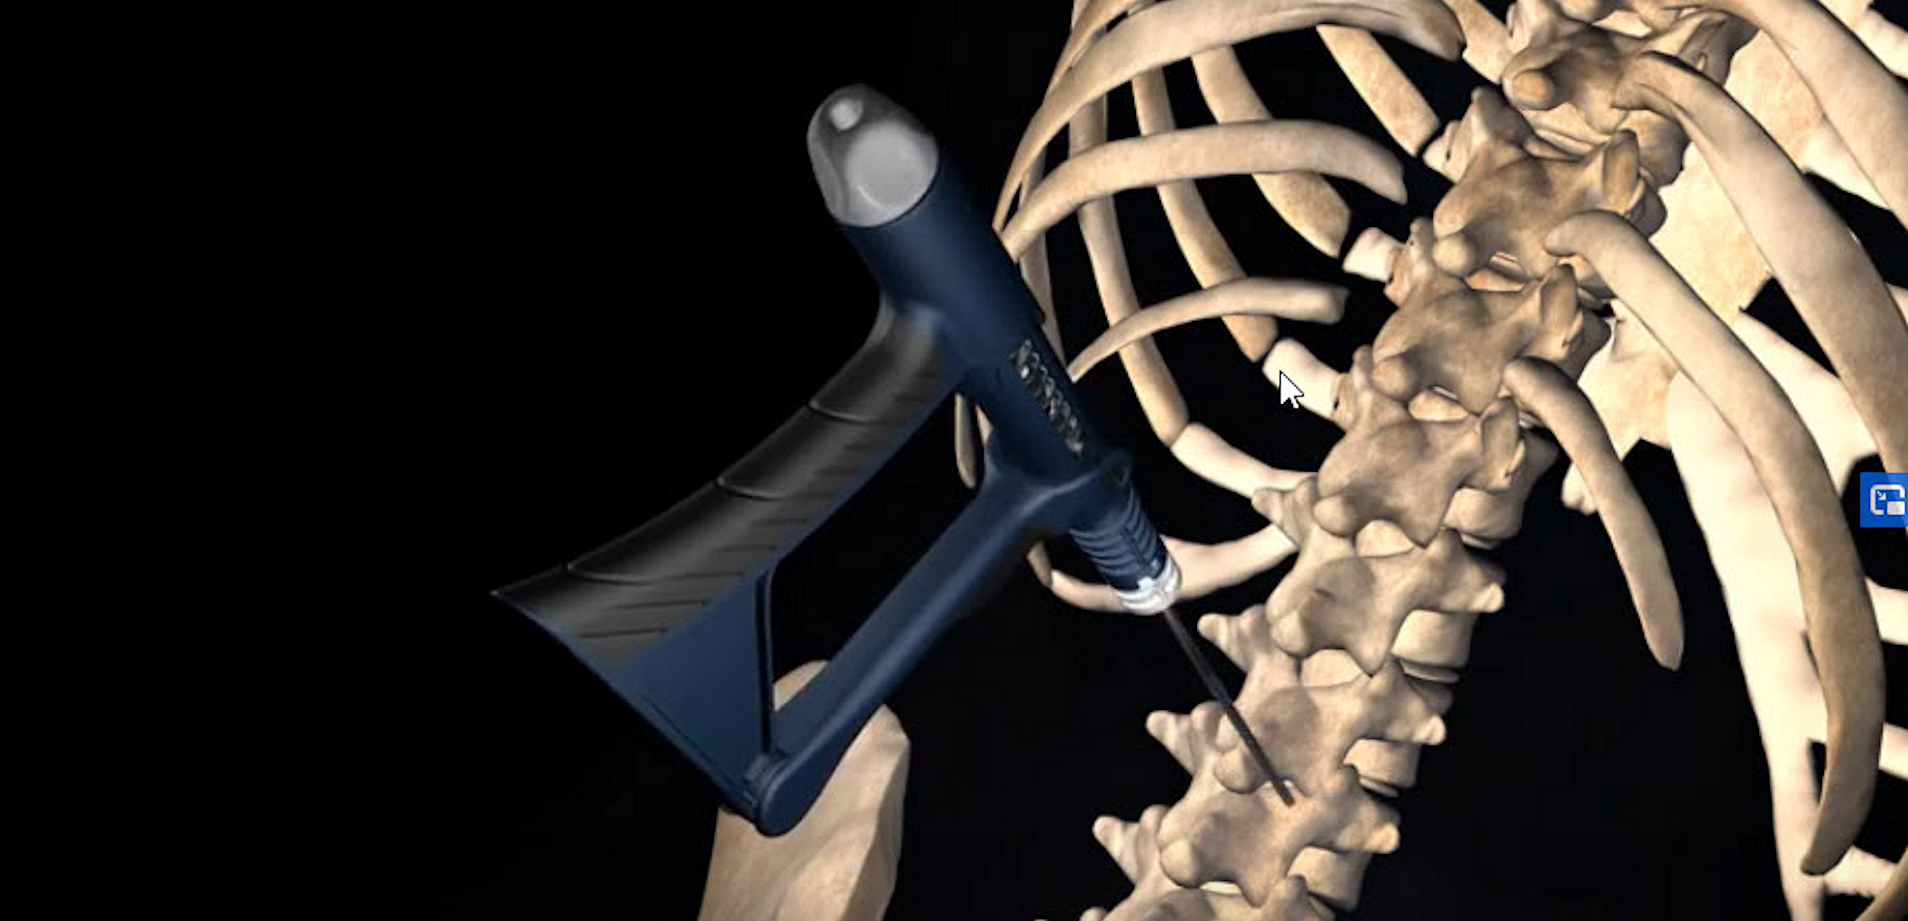

Certain bone access and bone biopsy procedures involve drilling into hard cortical bone, softer cancellous bone, and/or into intramedullary space.

The HAPTIX is a multi-use, rechargeable, high-torque electric tool with a novel SensorTech to help clinicians feel the difference between hard bone and soft bone/intramedullary space.

SensorTech is always-on, no extra buttons to press or enable, it senses change in bone density so clinicians can make millisecond decisions based on what they sense.

Beyond sensing, the reality of multi-use rechargeable tools is that sometimes the user is handed a fully charged device, other times the battery is on its last use. Clinically, sometimes users want the full force of electric power, other times clinicians want subtle facile control when drilling in a sensitive place.

To meet these challenges, HAPTIX also feature a novel AutoRatchet that allow users drill with the electric motor or manually ratchet a needle, drill bit, k-wire, or other.

Similar to SensorTech, no switches or extra buttons to press. AutoRatchet is always available so users can make a drill with a dead battery into a manual ratchet or instantly switch between drilling and ratcheting were soft manual actuation is needed.

HAPTIX also include a battery gauge and USB-C charging to help ensure charging success with millions of existing cords-set throughout the world.